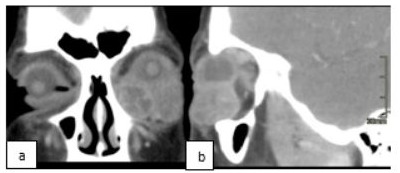

A twenty-two-year-old female presented with unpainful left lower eyelid swelling and double vision in the last 3 months before hospital admission. On examination her right eye Best Corrected Visual Acuity (BCVA) was 1.25 and 1.0 on the left, with left restricted eye movements in up-gaze direction, swelling of her left lower eyelid and chemosis. Optic nerve function and neuroophthalmological evaluation were normal. Computer topography scan of the orbit (CT) was performed at presentation showed a noncalcified, solid extra and intraconal mass with largest tumor diameter of 4 cm in the inferior half of the left orbit, with upward displacement of the globe. There was no evidence of intracranial invasion (Figure 1). Incisional biopsy histopathology showed embryonal rhabdomyosarcoma, spindle cell type with high degree of malignancy. Microscopically the tumor consisted of small spindle shaped cells to round rhabdoblast, immunohistochemistry tests were positive for desmin, myogenin, vimentin and myoD1.

Figure 1: CT, Coronal (a) and Sagittal (b) Section, before treatment (descrpition above).